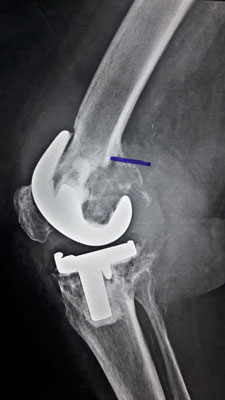

Revision Total Knee Replacement Surgery

Revision Total Knee Replacement means replacement of a joint which has already been replaced once before. There could be various causes for revision of the Primary Total Knee Replacement, but the most common cause is wear and tear of the earlier implant and excruciating knee joint pain.

Revision Total Knee Replacement is usually done for single Knee at one time. Care is taken that while removing primary implant, swabs are taken for culture to rule out infection. Also removing the primary implant may be difficult and could give rise to an iatrogenic fracture.